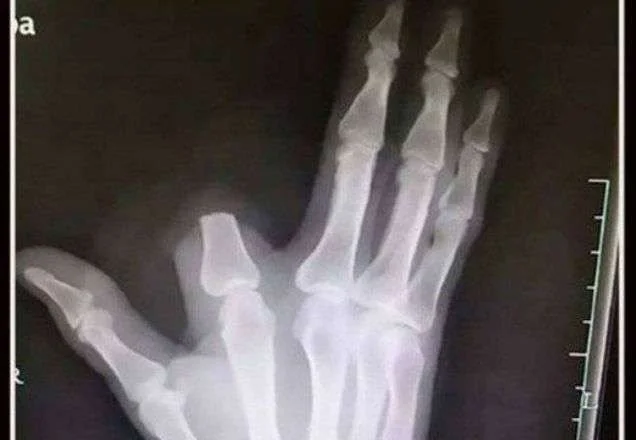

Os médicos explicaram que a amputação do dedo foi totalmente desnecessária e que, do ponto de vista médico, cortar um membro não impede a disseminação do veneno pelo organismo, uma vez que este entra rapidamente na corrente sanguínea. A situação tornou-se ainda mais trágica porque Zhang deixou o dedo amputado no local da picada, o que impossibilitou qualquer tentativa de reimplante.